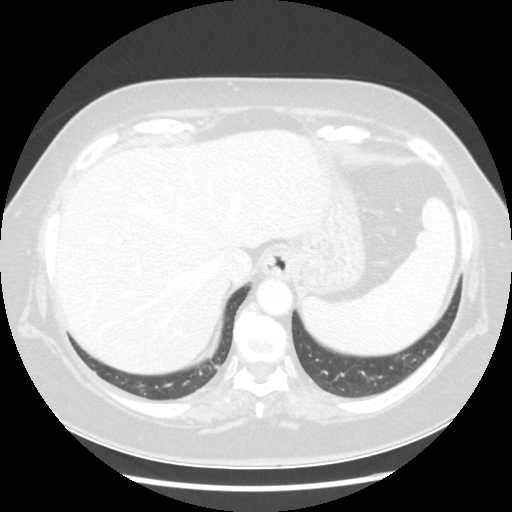

Original NATIVE CT scan (input)

Full window (WL 1023.5, WW 4095 β†’ Low βˆ’1024, High +3071)

Lung window (WL -600, WW 1500 β†’ Low βˆ’1350, High +150)

Mediastinum window (WL 40, WW 400 β†’ Low βˆ’160, High +240)